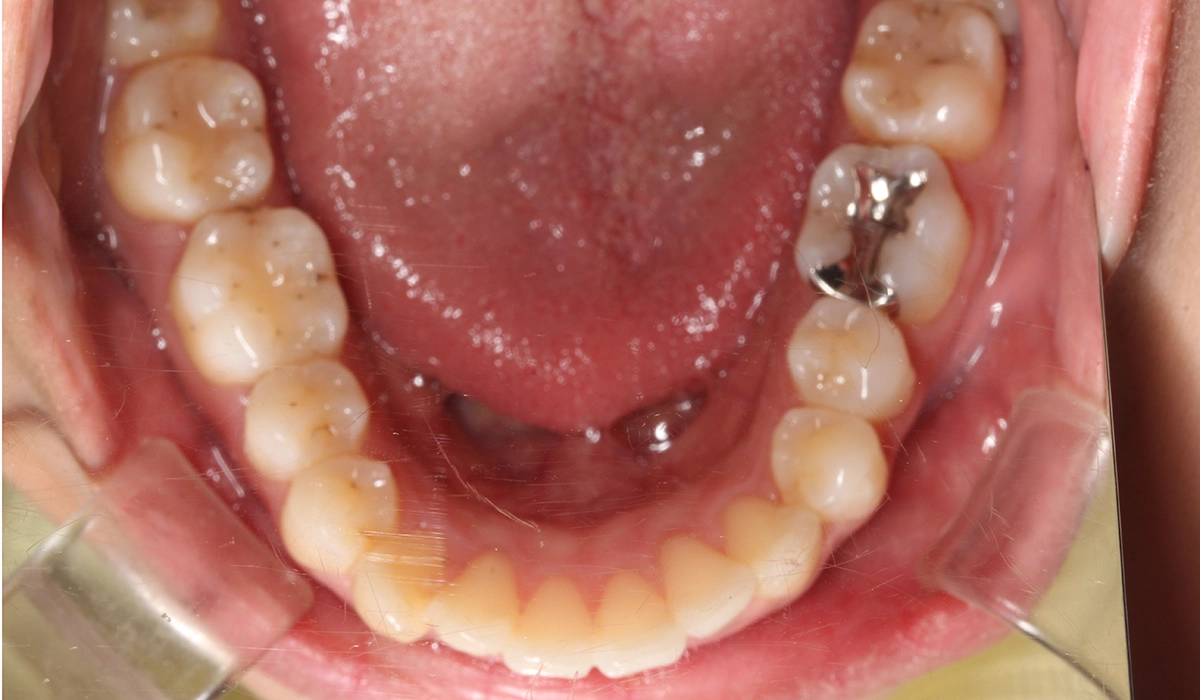

術前:下顎

術後:下顎